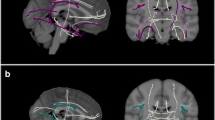

Thereafter, masks of the ATR, the cingulate bundle (CB) and the superior longitudinal fasciculus (SLF) (Fig. 1) were created using binarised regions of interest, which were based on the John Hopkins University White-Matter Tractography Atlas (Mori et al. 2005). To ensure value extraction in white matter only, the mask was applied to the mean FA skeleton. This confines the statistical analysis exclusively to voxels from the center of the tract, thereby minimizing anatomic inter-subject variability, registration errors, and partial volume effects. Averaged FA, MD, DA, and RD values of the regions of interest were used to examine group differences and the relation with inhibitory control.

The microstructure of cingulate bundle-, superior longitudinal fasciculus-, and ATR-white matter

Group comparisons using the averaged values of the cingulate bundle, the superior longitudinal fasciculus, and the ATR revealed for all but a few significantly decreased FA and increased MD, RD and DA in NF1 patients when compared to controls (Table 1). The averaged values of the FA, MD, RD, and DA of the CB, the SLF and the ATR showed differences between patients and controls in the range of 0.7 to 12.1 %, being most pronounced in the RD (Fig. 4). Also, large effect sizes (CB range: 0.7–1.2; SLF range: −0.3-1.2; ATR range: −0.8-(1.6)), which were associated with a high percentage of non-overlapping distributions were found (Fig. 4). To examine hemispherical differences in microstructural damage between left and right averaged CB, paired t-tests restricted to NF1 patients revealed differences in the FA (t(15) = 11.091, p < 0.001), RD (t(15) = −5.856, p < 0.001), and DA (t(15) = 3.162, p = 0.006), but not for MD (t(15) = −1.441, p = .170). In the SLF, FA (t(15) = 3.196, p = 0.006), MD (t(15) = −3.037, p = 0.008), and RD (t(15) = −3.738, p = 0.002), but not DA (t(15) = −0.394, p = 0.699) showed hemispherical differences. In the ATR, the FA (t(15) = 3.029, p = .008), MD (t(15) = −3.067, p = .008), and RD (t(15) = −.846, p = .002), but not the DA (t(15) = −.702, p = .494 ) showed significant differences between left and right hemisphere. All tracts indicate less microstructural damage to the left hemisphere, with the exception of the DA of the cingulate bundle. A similar effect was found in control subjects (CB: FA t(31) = 19.849, p < 0.001; MD t(31) = −2.134, p = 0.041; RD t(31) = −10.284, p < 0.001, DA t(31) = 7.867, p < 0.001; SLF: FA t(31) = 5.871, p < 0.001; MD t(31) = −4.385, p < 0.001; RD t(31) = −5.388, p < 0.001; DA t(31) = 1.572, p = 0.126; ATR: FA: t(31) = 5.832, p < 0.001; MD: U = −4.938, p < 0.001; RD: t(31) = −10.413, p < 0.001; DA: U = −3.009, p = 0.003).